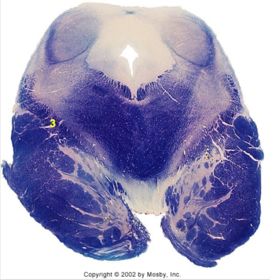

| Solitary nucleus | |

| ALS | |

| Medial lemniscus | |

| Medial longitudinal fasciculus | |

| Spinal tract of V | |

| Spinal nucleus of V | |

| Medial vestibular nucleus | |

| Inferior vestibular nucleus | |

| Dorsal cochlear nucleus | |

| Ventral cochlear nucleus | |

| Inferior olivary complex | |

| Inferior cerebellar peduncle | |

| CN IX | |

| Anterior spinocerebellar tract | |

| Central tegmental tract | |

| Olivary internal arcuate fibers | |

| Solitary tract | |

| Abducens root fibers | |

| Longitudinal pontine fibers (corticospinal tract) | |

| Transverse pontine fibers (dark fibers) | |

| Pontine nuclei (pale) | |

| Trapezoid body | |

| Ventral trigeminothalamic tract | |

| Superior olive | |

| Facial nerve root fibers - descending | |

| Facial motor nucleus | |

| Interposed nuclei | |

| Facial nerve root - internal genu | |

| Abducens nucleus | |

| Lateral vestibular nucleus | |

| Superior vestibular nucleus | |

| Superior cerebellar peduncle | |

| Dentate nucleus | |

| Fastigial nucleus | |

| Middle cerebellar peduncle | |